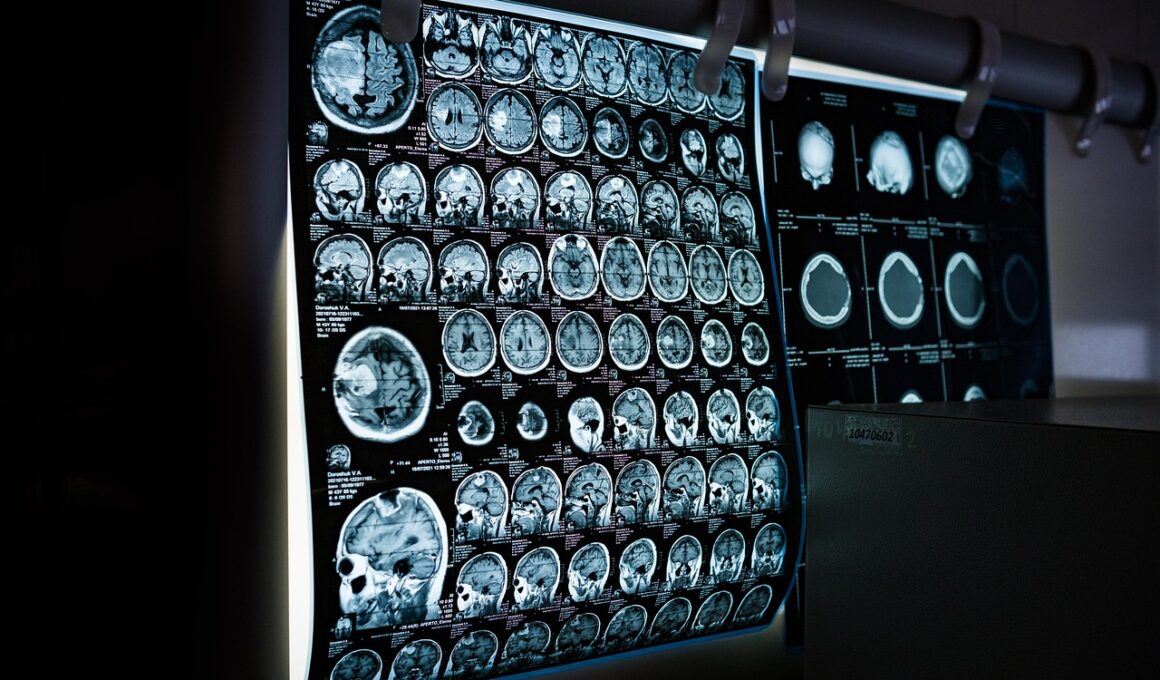

Sports injuries are a prevalent occurrence among athletes, affecting performance and overall well-being. The diagnosis of these injuries plays a crucial role in effective treatment decisions. Imaging techniques, such as X-rays, MRIs, and CT scans, are essential tools that provide detailed insights into the nature of these injuries. By allowing sports medicine professionals to visualize damaged tissues or bone structures, imaging facilitates accurate diagnoses. Early detection through imaging can lead to better recovery outcomes by identifying issues that might not be visible through physical examination alone. Failing to utilize imaging could result in misdiagnoses, delayed treatment, or even aggravation of the injuries, prolonging an athlete’s recovery. Athletes often depend on prompt and effective care, making it crucial for healthcare professionals to incorporate diagnostic imaging into their practice. Understanding the available imaging modalities is important for developing individualized treatment plans. Furthermore, ongoing advancements in imaging technology continue to improve diagnostic accuracy, which benefits athletes at all levels. Thus, imaging stands as a cornerstone in sports medicine, transforming how injuries are diagnosed and managed within the athletic community.

In the realm of sports medicine, practitioners often rely on several imaging modalities to identify and evaluate sports injuries. X-rays are commonly used to diagnose fractures or dislocations, providing a quick and clear view of bony structures. However, they may not always reveal soft tissue injuries such as ligament sprains or muscle tears. This is where MRI technology excels, offering high-resolution images of soft tissues, making it a preferred choice for diagnosing more complex injuries. Additionally, ultrasound is increasingly popular due to its real-time imaging capabilities, allowing doctors to assess dynamic movements in joints. Furthermore, CT scans combine the advantages of X-rays and MRIs, offering comprehensive views that can aid in surgical planning. Each imaging modality has its unique strengths and weaknesses, so choosing the right one is vital. Selecting the appropriate technique often depends on the type of injury and the specific details needed for diagnosis. Understanding these modalities is significant in guiding effective treatment strategies for athletes. Overall, imaging enables better-informed decisions regarding recovery and rehabilitation protocols.